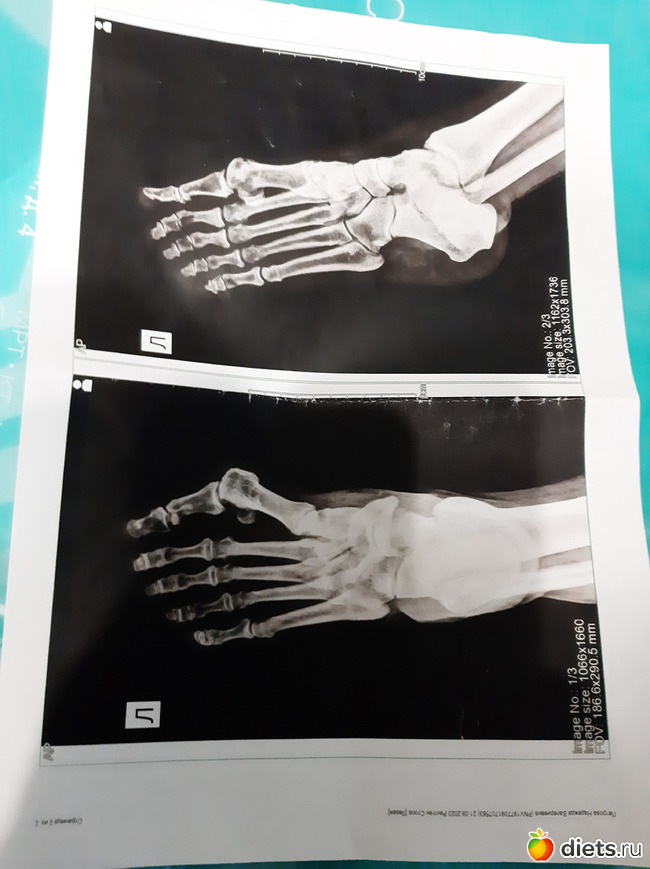

2.2 Нога - идём дальше

Теперь со снимками и заключением к ортопеду, что он скажет.

Здоровья тебе, палец на рентгене выглядит подозрительно, хотя я не доктор.

Да палец-то понятно, вальгус, меня больше беспокоит сейчас стопа сверху, я как-то писала, она выгибаться начала

А со стопой - выздоровею и поеду к ортопеду

Прикольно так вот на рентгене свои косточки посмотреть! интересно...я помню, когда мне делали узи брюшной полости, попросила экран ко мне повернуть

проблема с пальцем прям чётко видно у тебя

Да палец я же с ортезами, у меня же свод стопы подниматься стал.